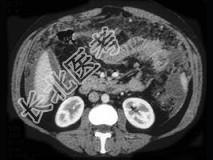

- 单项选择题女,36岁, 低热、乏力,腹胀不适1月余, 结合影像检查,应考虑为  (    )

- A、肝硬化腹水

- B、结核性腹膜炎

- C、腹腔转移瘤

- D、心源性腹腔积液

- E、急性化脓性腹膜炎